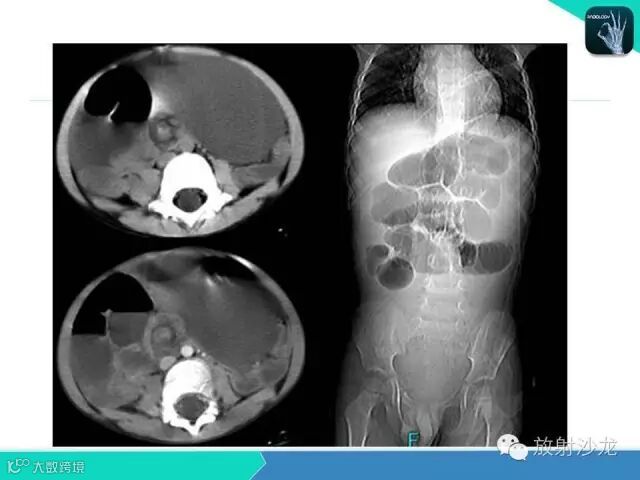

肠梗阻的分类及影像诊断